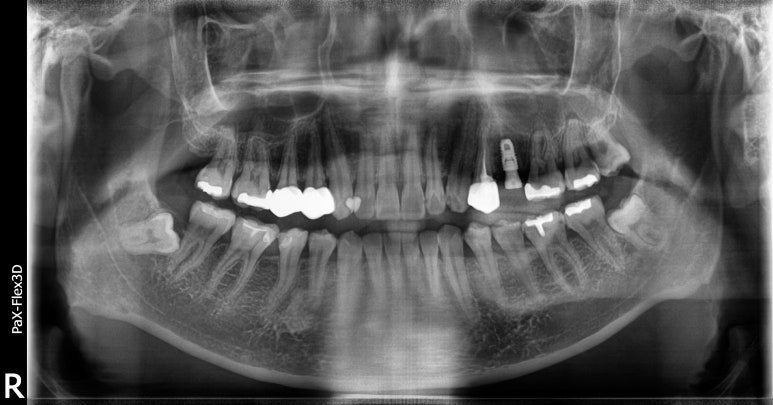

정확한 진단을 위해 파노라마 엑스레이와 CT를 촬영해보니 잇몸에 염증이 다소 있는 것을 확인했습니다.

해당 치아는 이미 신경치료 후 크라운을 씌운 후 사용하던 치아라 이미 염증이 생겼다면 발치가 불가피한 것으로 판단했습니다.

그래도 환자분은 잇몸에 염증은 있지만 심하지는 않아서 내원하신 당일 발치즉시임플란트 수술 진행했습니다.

다만, 잇몸뼈가 다소 녹아있어 당일식립하면서 뼈이식도 함께 진행해주었습니다.

발치즉시임플란트와 동시에 뼈이식을 진행하는 수술은 난이도가 굉장히 높은 수술인데요.

다행히 환자분은 수술이 잘 마무리되었고, 보철물까지 무사히 부착이 완료되었습니다.